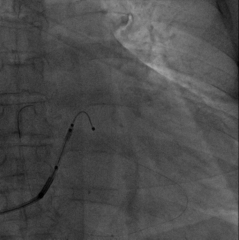

选择后侧静脉,Runthough导丝顺利通过并与心中静脉交通回到右心房,但左室4298电极无法通过狭窄处。

因4298外径在5.3F,故选用Maverick2.0X15mm预扩球囊在狭窄处给予充分扩张

扩张后电极仍无法通过

尝试心中静脉,但血管扭曲,导丝进入困难

尝试侧静脉,但远端过于狭窄,电极无法完全进入分支,测试结果不理想,只能放弃该血管

再次尝试后侧静脉,改用Sprinter Legend2.5X15mm预扩球囊扩张,可见明显腊肠样狭窄,给予28atm时方可见完全扩张

电极仍然无法通过,造影发现狭窄依然存在

尝试鞘中鞘试图通过狭窄处,但电极仍然无法通过

尝试Quantum Maverick3.0X12mm后扩球囊进行扩张

电极依然无法通过狭窄处,放弃手术?